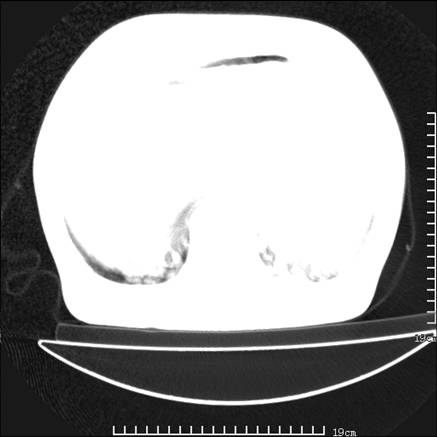

张男,75岁,干咳半年余,小便不利二年,b超检查前列腺增大,未见明显肿块;前列腺癌血生化检查多项指标明显增高。

双肺内多发转移瘤,纵膈淋巴结转移。来源前列腺?建议盆腔mri进一步检查。